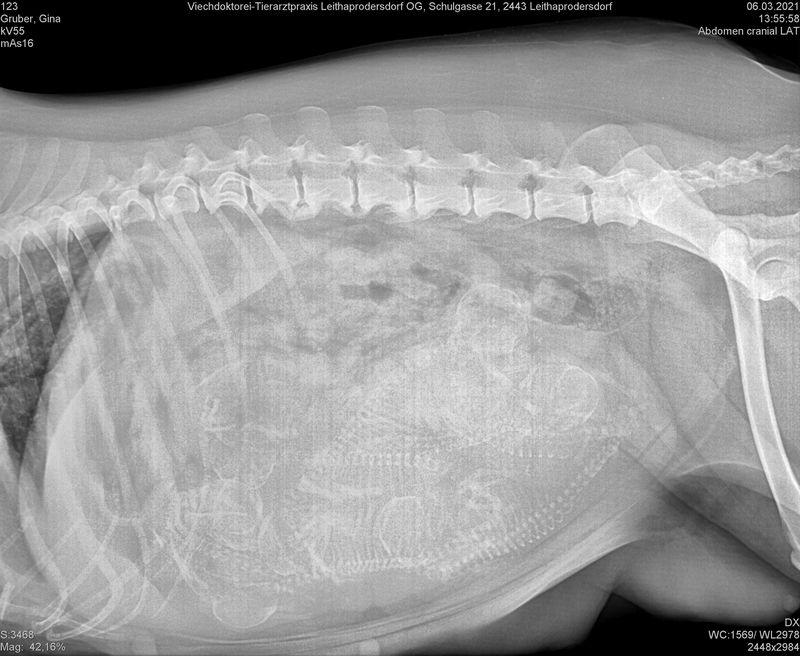

06.03.2021 Erster "Blickkontakt" (Röntgenbild)

- wer erkennt, wie viele es sind?